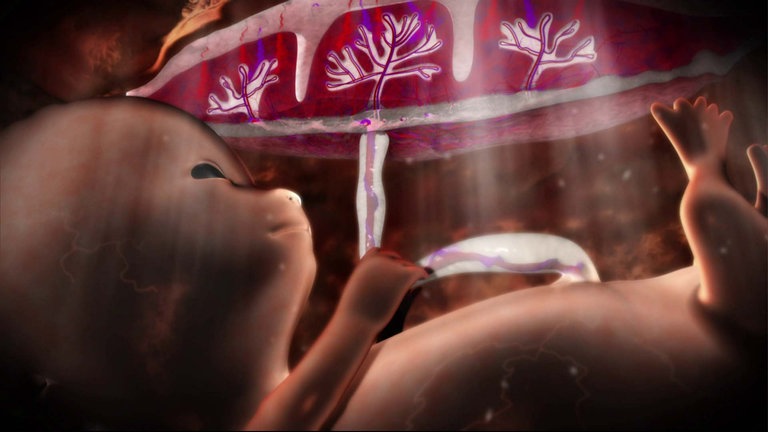

Wie finden sich Spermium und Eizelle? Wann werden im Embryo welche Organe angelegt? Wie verändert sich der Fötus im Verlauf der neunmonatigen Schwangerschaft? Dieser Film porträtiert die Entstehung menschlichen Lebens von der Befruchtung bis zur Geburt.

Wir begleiten die schwangere Sabrina und ihre kleine Tochter Ronja auf ihrem Weg zu Ultraschalluntersuchungen, Schwangerschaftsgymnastik. Mit Sabrina gehen wir dann in den Kreißsaal. Aufwändige Computer-Animationen zeigen die Anatomie der Geschlechtsorgane, illustrieren die Arbeitsweise von Nabelschnur und Plazenta und veranschaulichen ausgewählte Entwicklungsschritte des Kindes im Mutterleib.